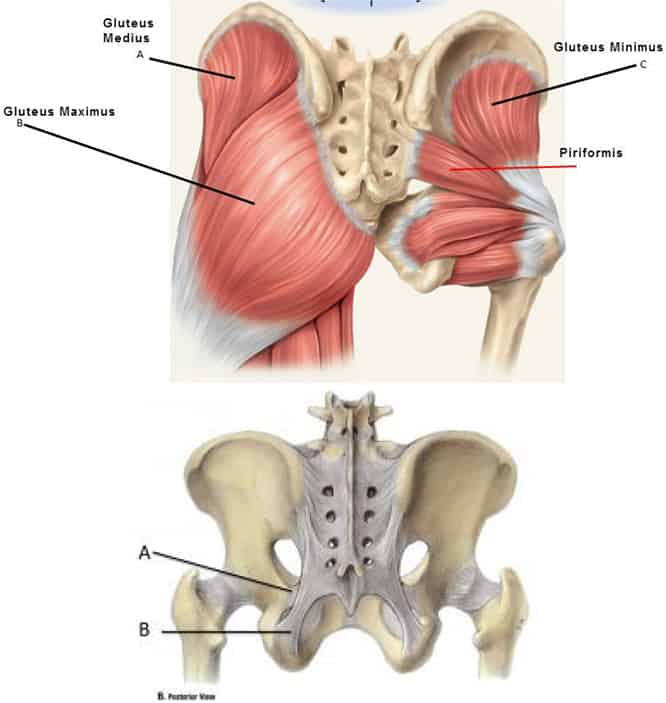

Анатомия мышц: Пириформис